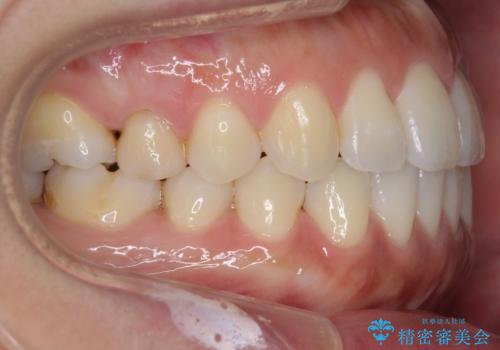

受け口、すきっ歯を インビザラインで モニター治療

- 前歯のすき間と受け口を気にして来院。

マウスピースでしっかり閉じています。

下の前歯を後方に移動するため、ゴムを上下のマウスピースにかけてもらいました。